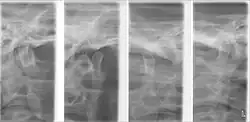

Plain radiography

This method of imaging allows the visualisation of the joint's mineralised areas, therefore excluding the cartilage and soft tissues.[56] A disadvantage of plain radiography is that images are prone to superimposition from surrounding anatomical structures, thereby complicating radiographic interpretation.[56] It was concluded that there is no evidence to support the use of plain radiography in the diagnosis of joint erosions and osteophytes.[57] It is reasonable to conclude that plain film can only be used to diagnose extensive lesions.[57]